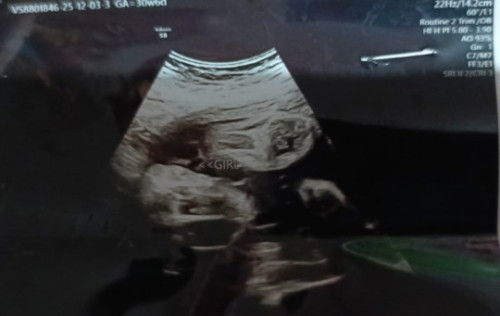

PERMISSION TO POST.

Hello po, goodmorning mga momsh. ask lang po normal po ba results ko. Dipo kc nabasa ng OB ko today gawa po ng wla sya! may emergency po. Gusto ko lang po malaman sana yng results if marunong po kayo magbasa salamat po.